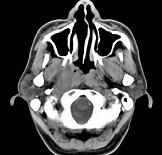

男,52岁,血涕二月余,CT如图所示,最可能的诊断为()A.鼻咽癌B.咽旁混合瘤C.咽部神经纤维瘤D.小涎液腺瘤E.咽旁脓肿

问题 男,52岁,血涕二月余,CT如图所示,最可能的诊断为()

选项 A.鼻咽癌 B.咽旁混合瘤 C.咽部神经纤维瘤 D.小涎液腺瘤 E.咽旁脓肿

答案 A